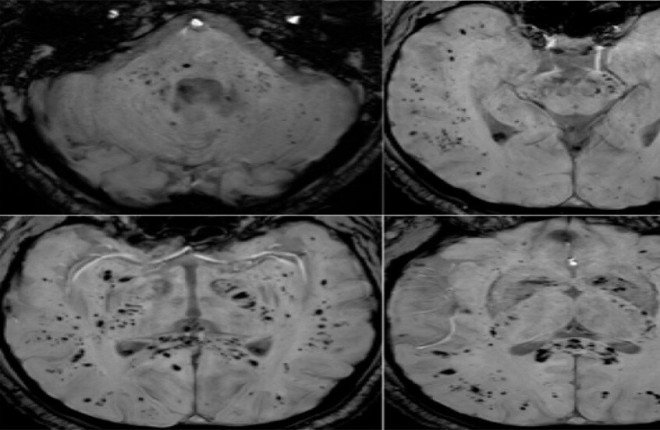

نُشرت الدراسة في مجلة Brain, Behavior, & Immunity Health، وتستند إلى تحليل صور الرنين المغناطيسي لأدمغة مجموعة من المتعافين من كوفيد-19. أجريت الأبحاث على أشخاص من مختلف الأعمار ومستويات شدة الإصابة، مما يوفر رؤى شاملة حول تأثير الفيروس على الدماغ. تأتي هذه النتائج في وقت يزداد فيه القلق بشأن الأعراض طويلة الأمد المرتبطة بـ كوفيد-19، والمعروفة أيضًا باسم “كوفيد طويل الأمد”.

استخدم فريق البحث تقنيات تصوير الرنين المغناطيسي المتقدمة لتحليل المادة الرمادية والمادة البيضاء في الدماغ. المادة الرمادية مسؤولة عن معالجة المعلومات، بينما تلعب المادة البيضاء دورًا حاسمًا في توصيل الإشارات بين مناطق الدماغ المختلفة. وفقًا للدكتور كيران تاباليا، الباحث الرئيسي في الدراسة، أظهرت النتائج اختلافات واضحة في كلتا المادتين لدى المتعافين من كوفيد-19.

أظهرت الدراسة انخفاضًا في حجم بعض مناطق الدماغ، خاصة تلك المرتبطة بالذاكرة والوظائف الإدراكية. بالإضافة إلى ذلك، لوحظت تغييرات في بنية المادة البيضاء، مما قد يؤثر على كفاءة الاتصال العصبي. هذه التغيرات الهيكلية قد تفسر بعض الأعراض العصبية طويلة الأمد التي يعاني منها العديد من المتعافين من كوفيد-19، مثل صعوبة التركيز وضعف الذاكرة.